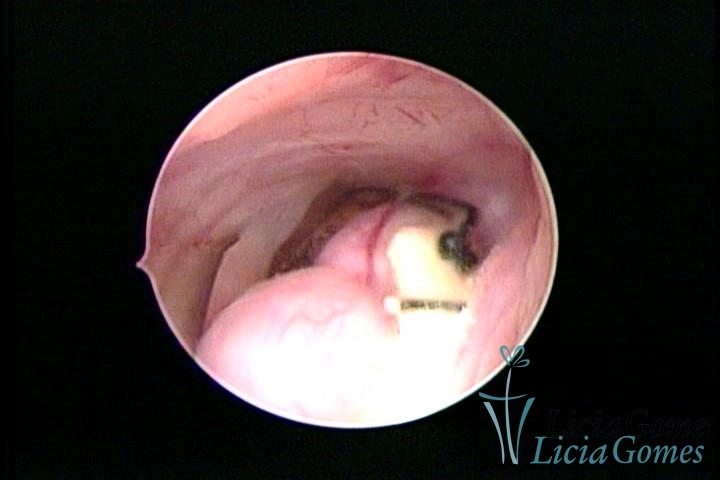

Mirena device® and a submucous myoma

×